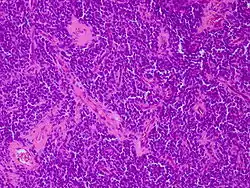

![]() صورة مجهرية لورم الأديم العصبي الظاهر البدائي مصبوغة بالهيماتوكسيلين واليوزين. صورة مجهرية لورم الأديم العصبي الظاهر البدائي مصبوغة بالهيماتوكسيلين واليوزين. | |

يحصل الورم على اسمه لأن غالبية الخلايا في الورم مشتقة من الأديم العصبي، لكنها لم تتطور وتتميز في الطريقة التي يتطور بها العصبون الطبيعي، وبالتالي تظهر الخلايا "بدائية".

باستخدام النقل الجيني لمضاد T-SV40 الكبير في خلايا السلائف العصبية للفئران، تم إنشاء نموذج ورم في الدماغ. كان ورم الأديم العصبي الظاهر البدائي لا يمكن تمييزه من الناحية النسيجية عن نظيراته البشرية، وقد تم استخدامها لتحديد الجينات الجديدة المشاركة في سرطانة ورم الدماغ البشري.[3]